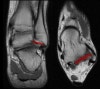

4. Anterior Tibiofibular ligament

Coronal (left) and axial (right) T1W images assessing the distal anterior tibiofibular ligament which is thickened but intact due to a previous injury in this patient.